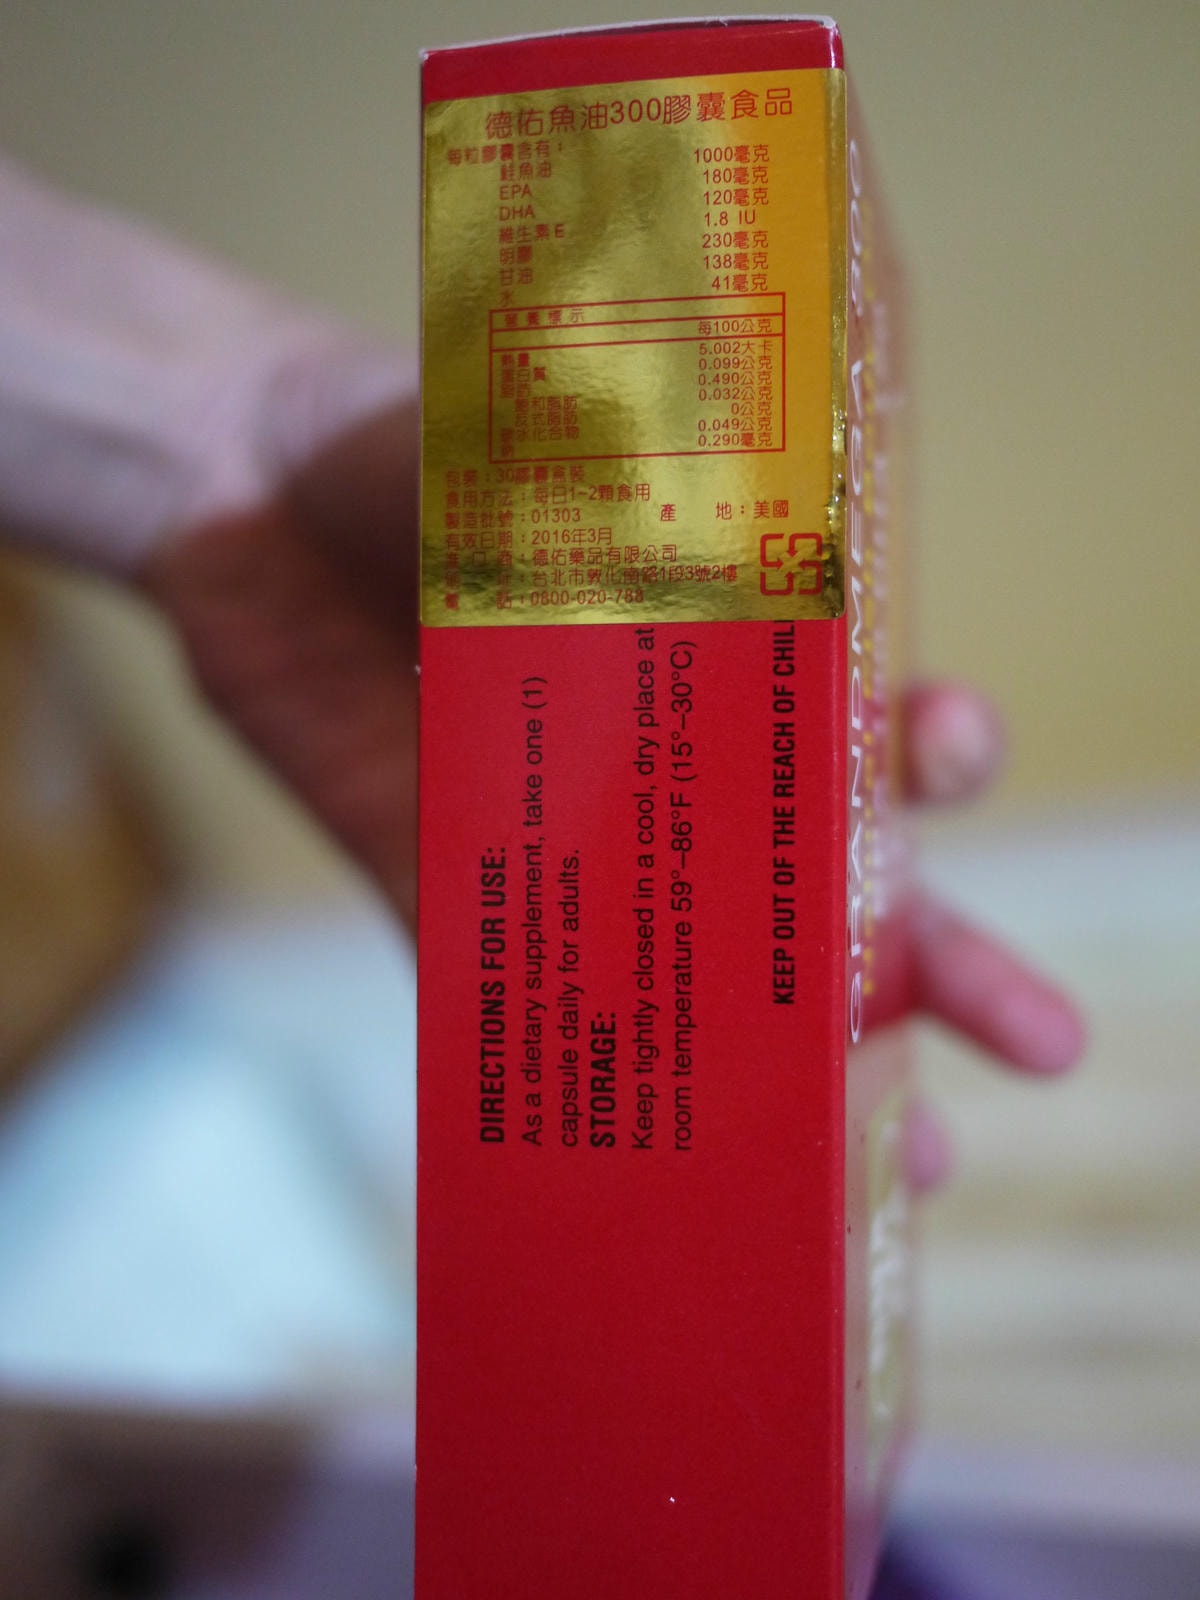

醫生說32週前都還可以吃動物性的DHA,32週後就要改吃植物性的DHA,避免生產時會抗凝血

4~6個月左右我都吃中間藍色這款歐洲的DHA膠囊,用吞的用嚼的都可以

用嚼的還會有甜甜的橘子香

大約吃到25週左右第一盒DHA就吃完啦!之後我又加買了比較小盒的DHA

想說大概30週就換成植物性的DHA好啦

此款DHA為美國製造

此款DHA膠囊比前次吃的膠囊還要大顆,感覺也比較硬一點點